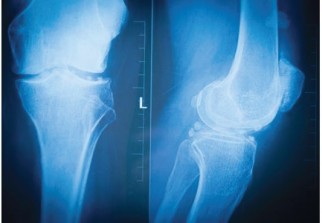

La gonarthrose touche 3,5 millions de Français, soit 1 sur près 10 millions de Français atteints d' arthrose . Trop souvent considérée comme une simple usure liée au vieillissement, l'arthrose est une véritable maladie qui, si elle ne se guérit pas, se soigne. Cette maladie implique les trois tissus de l'articulation : le cartilage, l'os sous chondral (zone osseuse située sous le cartilage) et la membrane synoviale qui tapisse l'intérieur de l'articulation.

Assez fréquente à partir de l'âge de la ménopause (vers 50 ans en général), l'arthrose du genou correspond à une "érosion" du cartilage de l'articulation fémorotibiale, ce revêtement protecteur qui permet au fémur, à la rotule et au tibia de bien coulisser les uns contre les autres - mais sans se toucher. En cas d'arthrose, les os "frottent", ce qui provoque une douleur. À terme, une prothèse peut même être nécessaire.